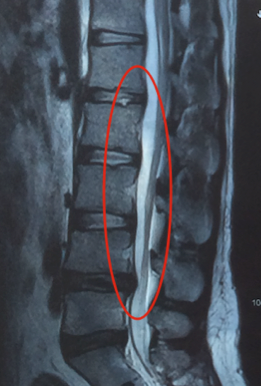

Natomiast wypuklina krążka kręgowego polega na odkształceniu włóknistego pierścienia krążka międzykręgowego, bez wychodzenia jego zawartości (ryc. 3).

Ryc. 3